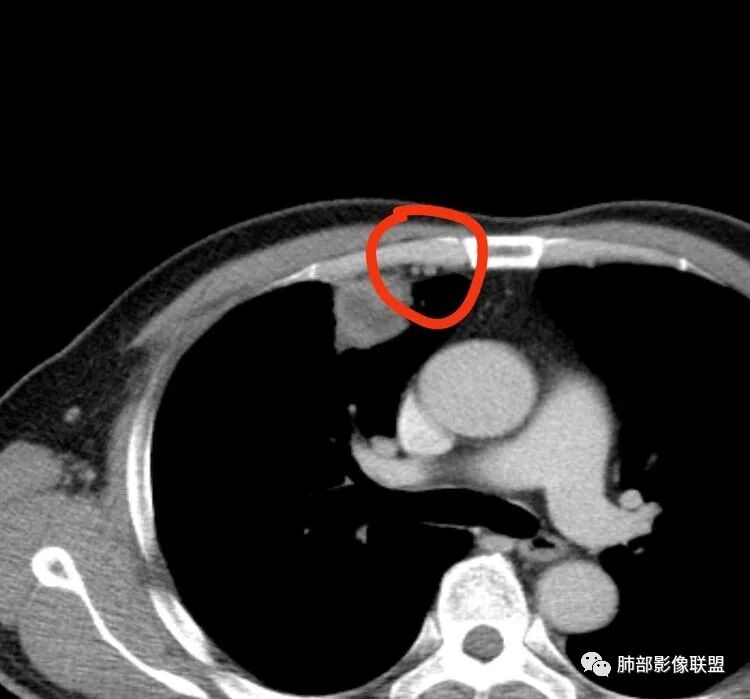

患者,男,52岁主诉:咯血6小时既往史:否认高血压、糖尿病等。定位在哪?

水平裂以上,上叶前段,先看周围,非远端有斑片状高密度影。

边缘平直、稍凹陷,部分区域膨隆。

宽基底与胸膜相连,附近胸膜稍增厚。

支气管进入病灶内,近端堵塞,断端圆钝。

支气管壁均匀稍增厚。

回顾性分析本病例,小编觉得鉴别诊断聚焦于肺鳞癌和炎性病灶(包括结核)之间,这个病灶的炎性征象大于恶性征象;以下是这个病例的的炎性征象:①病灶边缘平直收缩为主,也缺少典型的分叶毛刺;②支气管走行于病灶中央截断,断端比较圆钝;③近端引流支气管壁增厚;④整体强化不显著,坏死区太圆太规整,边缘隐约显示强化的环;⑤血管走形自然,未见明显破坏征象;⑥胸膜外脂肪间隙增宽,胸膜广基地增厚,未见栽赃;⑥52岁偏年轻(此条也不大支持鳞癌)

虽然本例患者支气管截断,病灶中央截断炎性及恶性都可以,断端向病灶一侧圆钝更支持炎性。